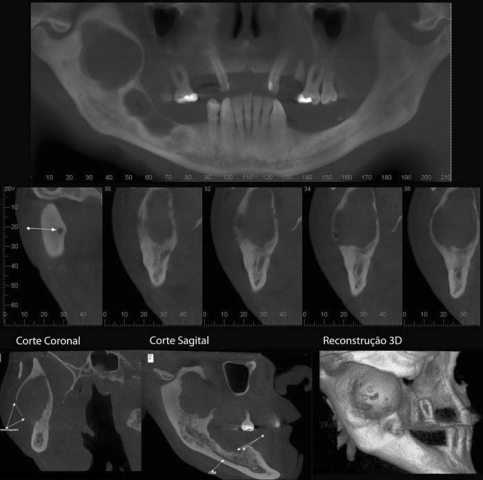

CASO 1 - Anquilose de ATM

Paciente com assimetria, limitação de abertura bucal. Observa-se união óssea da porção posterior e lateral do côndilo ao esfeóide e zigomático.

CASO 3 - Fratura de ATM

Paciente com história clínica de trauma. Fratura no côndilo direito com deslocamento do fragmento para medial e deslogamento do côndilo para lateral da cavidade articular.